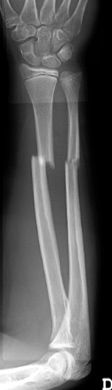

Las fracturas de ambos huesos del antebrazo al mismo nivel, con líneas de fractura oblicua-transversa o desplazamiento convergente son inestables y precisarán de tratamiento quirúrgico. En estos casos está indicado, dependiendo de la edad del paciente, el tratamiento mediante reducción y osteosíntesis. El enclavado intramedular elástico es el tratamiento de elección (Figura 15).

Figura 15: a-Imagen clínica de fractura de antebrazo derecho con gran deformidad. b- Radiografía donde se aprecia fractura de radio-cúbito de trazo transverso en el mismo nivel. c, d-Enclavado intramedular elástico. e,f- Imagen final con buena consolidación ósea.